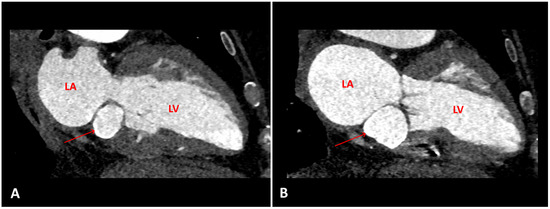

Figure 1.

A. transthoracic echocardiogram, two-chamber view showing a posterior mitral annulus caseous calcification (arrow), which appears as a well-defined brightened edge corresponding to an echodense periphery, and a central echolucent area corresponding to the central liquefaction. B. Computed tomography scan, showing a well-defined oval or crescent-shaped hyperdense mass with peripheral calcification (arrow). C. Late gadolinium enhancement-magnetic resonance imaging sequence, showing caseous calcification of the mitral annulus as a hypointense zone without late gadolinium enhancement (arrow). LV: left ventricle; LA: left atrium

A routine transthoracic echocardiogram (TTE) performed 4 years previously, with a view to orthopaedic surgery, had revealed a cardiac mass attached to the posterior mitral annulus with a mitral mean gradient of 6 mm Hg (at a heart rate of 80 beats per minute). At that time cardiac magnetic resonance imaging (cMRI) and computed tomography (CT) were performed and the diagnosis of caseous calcification of the mitral annulus was established (

Figure 1). Two years after the initial diagnosis, the patient developed third degree atrioventricular block for which a dual-chamber pacemaker was implanted. The patient was asymptomatic for a further 2 years until she developed an episode of acute severe dyspnoea.